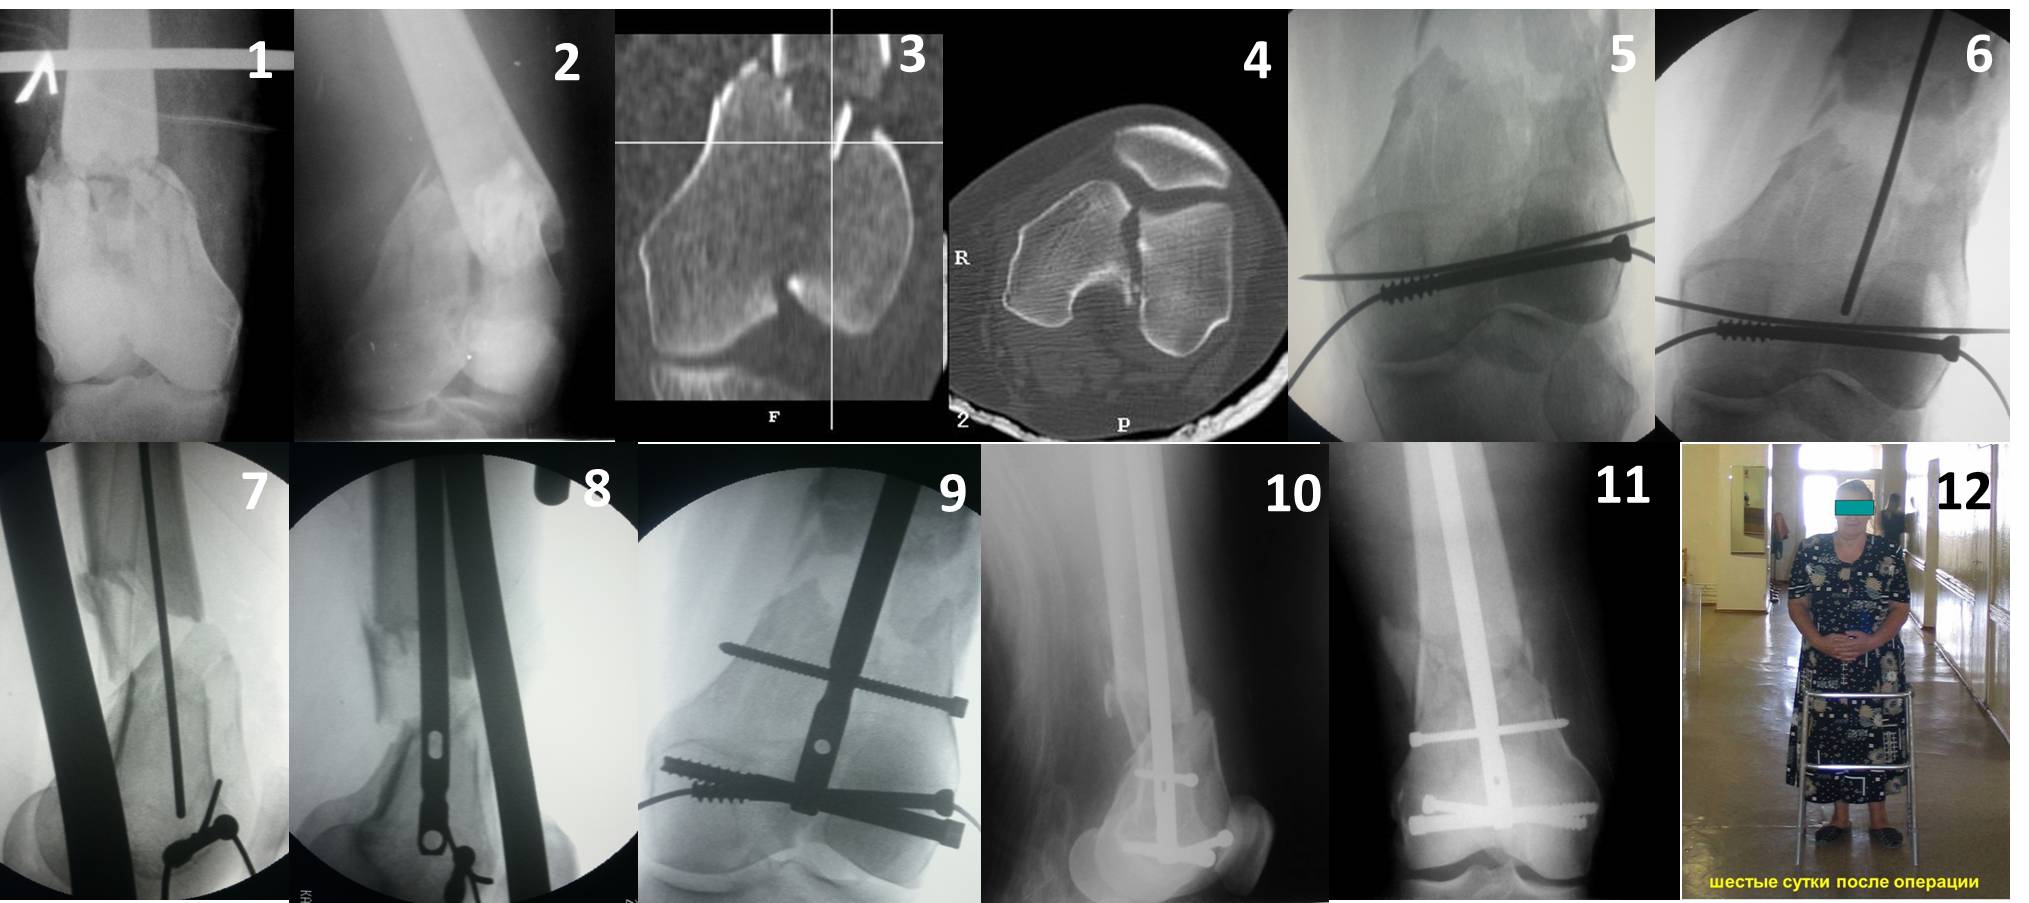

Ответ на эту часть Вашего поста – вложенный файл. Больная оперирована неделю назад по поводу открытого перелома дистального эпиметафиза бедренной кости. После операции она идёт в рентгенкабинет для выполнения послеоперационной контрольной рентгенографии, представленной на слайдах 10 и 11. Узнав, почему её фотографируют, просила передать Вам, Антон, привет.

наружный мыщелок не дорепонироавн - это приводит к вальгусной деформации оси коленного сустава, очень критично для последующей функции.

Антеградное штифтование не очень годится при переломах типа C3, когда есть многооскольчатость именно суставной поверхности. А при переломах типа C1 и С2, т.е. и в обсуждаемом случае тоже, он как раз вполне оптимален. На межфрагментарную компрессию как-то не приходилось так драматически полагаться при интрамедуллярном остеосинтезе, результаты хорошие без нее были.

В этой терминологии мы, получается, создавали компрессию встречными спицами с упорами или reduction clamps, а потом вполне обходились запирающими винтами как позиционными. Бывает, проводим 1-2 спонгиозных винта 6,5-8 мм - вот они вполне компрессирующие.

И уже лет шесть мы используем возможность ввести в дистальное овальное отверстие 3 винта, которые именно запираются в этом отверстии, не люфтят, а обеспечивают угловую стабильность - см картинку.

Получается и стабильно, и очень дистально, нижний край отверстия в 3 мм от дистального конца гвоздя.

В приложении пример недавней операции, C3, открытая репозиция, фиксация мыщелков спицами и винтами, ретроградный синтез большеберцовым гвоздем 10,5 мм диаметром, винты 5 мм.